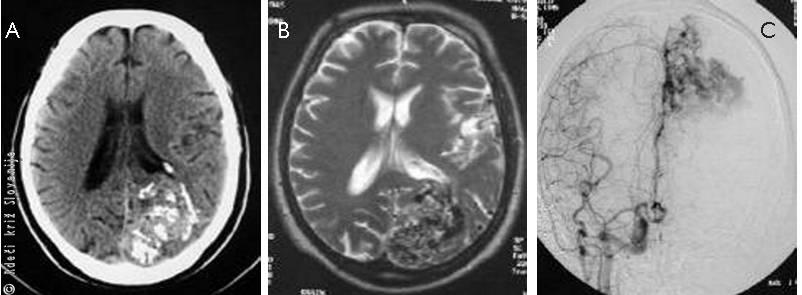

Slika 11

Subarahnoidna krvavitev:

A – Nastala zaradi arterio-venske malformacije – bolezensko spremenjene arterije in vene prikazane na računalniški kontrastni žilni preiskavi možganskih žil.

B – Prikaz z magnetnoresonančnim tomografskim slikanjem.

C – Prikaz s kontrastno žilno preiskavo možganov.